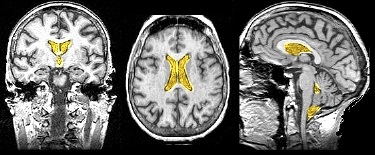

Ventricles {W} and

Cerebral Spinal Fluid (Spector et al. 2015)

The ventricles and surrounding areas of the brain are spaces that are filled with a clear fluid (cerebrospinal fluid [CSF]).

CSF is a clear, colorless, watery substance that is derived from blood plasma (to which it is similar). Normally, there are no red blood cells and very few white blood cells in the CSF. At any one time, there is about 125-150 mL (4-5 oz.) in the brain and, each day, the choroid plexus produces about 500 mL (17 oz.) of CSF which flows continuously. The CSF is reabsorbed into the blood stream by the arachnoid granulations in the subarachnoid space of the meninges at the top of the brain. (see diagram on right).

Hydrocephalus: Blockage of the flow of CSF in brain of infant causing swelling of head and, usually, intellectual deficiencies.

- Purposes of CSF: The CSF serves as a shock absorber or cushion as well as a support for the weight of the brain.

- CSF provides a range of nutrients (hormones, vitamins).

- CSF removes metabolic and other waste materials from the brain.

- Origin: CSF is formed by cells (the choroid plexus) inside the brain's ventricles

- Flow of CSF: Lateral to third to fourth ventricles. Then,

- Some CSF into the central canal of the spinal cord, while

- Other CSF flows into the space between the brain and the tissue which covers the CNS (meninges). The CSF is then reabsorbed in the subarachnoid space back into the blood.